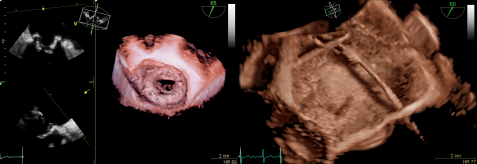

4.HDlive内腔镜四维成像技术:

HDlive先进的四维成像呈现方案,通过模拟光源在组织中传播和散射的原理,增强可视化成像效果,以外科视野方式,便于更好理解四维立体结构,以用于临床诊断与治疗效果评估

5两点剪切技术(2-ClickCrop):

任意点击、简单拖拽,“一点一拉”间轻松获取任意心脏结构的四维图像。通常在实时扫描和存储的图像中显示标准和非标准的切面相当困难。而两点剪切技术是一种简单、快速、直观的实时成像工具,只需要在二维或四维图像中确定两点位置,即刻帮助您快速且简便地提取结构中的非标准视图,即刻实现四维成像。这一技术真正帮助我们将四维成像变得如二维成像般简单,协助我们把四维成像技术真正的应用于临床日常工作。